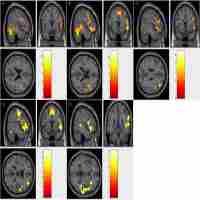

| Abstract | Patients with lesions in or near eloquent cortex typically undergo one of several invasive techniques to prevent loss of function following surgery. One of the most promising potential clinical applications of functional magnetic resonance imaging (fMRI) is to map these functions as part of the pre-surgical work-up to identify patients at-risk, guide the surgical entry, or tailor the surgical procedure to prevent deficits. While motor and sensory mapping are relatively straightforward, language mapping is far more complex. The language system is variable in location across individuals and in many cases may reorganize partially or completely to the contralateral hemisphere. In addition, multiple regions of the brain contribute to language functioning including essential regions that must not be removed in surgery, and contributory regions that may result in transient or insignificant impairments post-surgery. Despite these challenges, an increasing number of studies have supported the use of fMRI for pre-surgical language mapping in a variety of disorders. This article reviews the literature from three disorders for which patients benefit from preoperative language mapping: epilepsy, brain tumors, and arteriovenous malformations. Each disorder presents unique challenges to language mapping. Specific case studies are presented highlighting the both the potential benefits of preclinical fMRI for language mapping as well as the potential risks and pitfalls. |